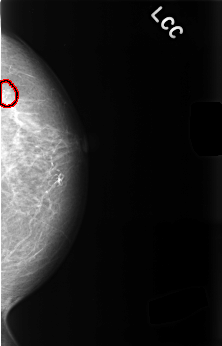

Digital Database for Screening Mammography

Volume: benign_14 Case: C-0476-1

C_0476_1.LEFT_CC

LEFT_CC LINES 4496 PIXELS_PER_LINE 2880 BITS_PER_PIXEL 12 RESOLUTION 50 OVERLAY

FILE: C_0476_1.LEFT_CC.OVERLAY

TOTAL_ABNORMALITIES 1

ABNORMALITY 1

LESION_TYPE CALCIFICATION TYPE PLEOMORPHIC DISTRIBUTION CLUSTERED

ASSESSMENT 4

SUBTLETY 4

PATHOLOGY BENIGN

TOTAL_OUTLINES 1

BOUNDARY